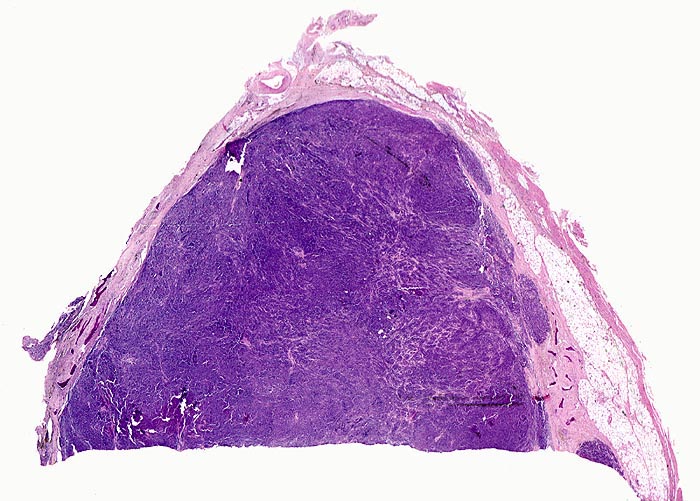

Plasmazellmyelom

Knochenmark, Wirbelkörper

Von schmalen bindegewebigen Septen durchzogene solide basophile Tumormasse ohne erkennbare Markstrukturen. Im Randbereich sind einzelne Knochenbälkchen erkennbar.

Notfalleinweisung wegen umschriebenen Thoraxschmerzen ohne adäquates Trauma. Im Röntgenbild Nachweis multipler Frakturen der Wirbelsäule und der Rippen bei grobsträhniger Osteoporose. In der Serumelektrophorese Nachweis einer Paraproteinämie.

Diagnosesicherung: Immunhistologischer Nachweis von monoklonalem Immunglobulin (IgG oder IgA und kappa- oder lambda-Leichtketten in einem Verhältnis von >1:16 bzw. >16:1). Klinisch entsprechender Nachweis einer Paraproteinämie oder Proteinurie (Bence-Jones Protein = monoklonale freie Leichtketten).

Histologie

Scan